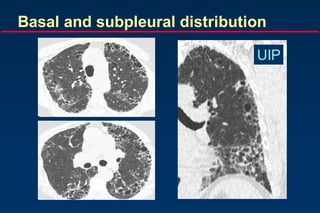

Basal and subpleural predominance

Basal and subpleural distribution

UIP